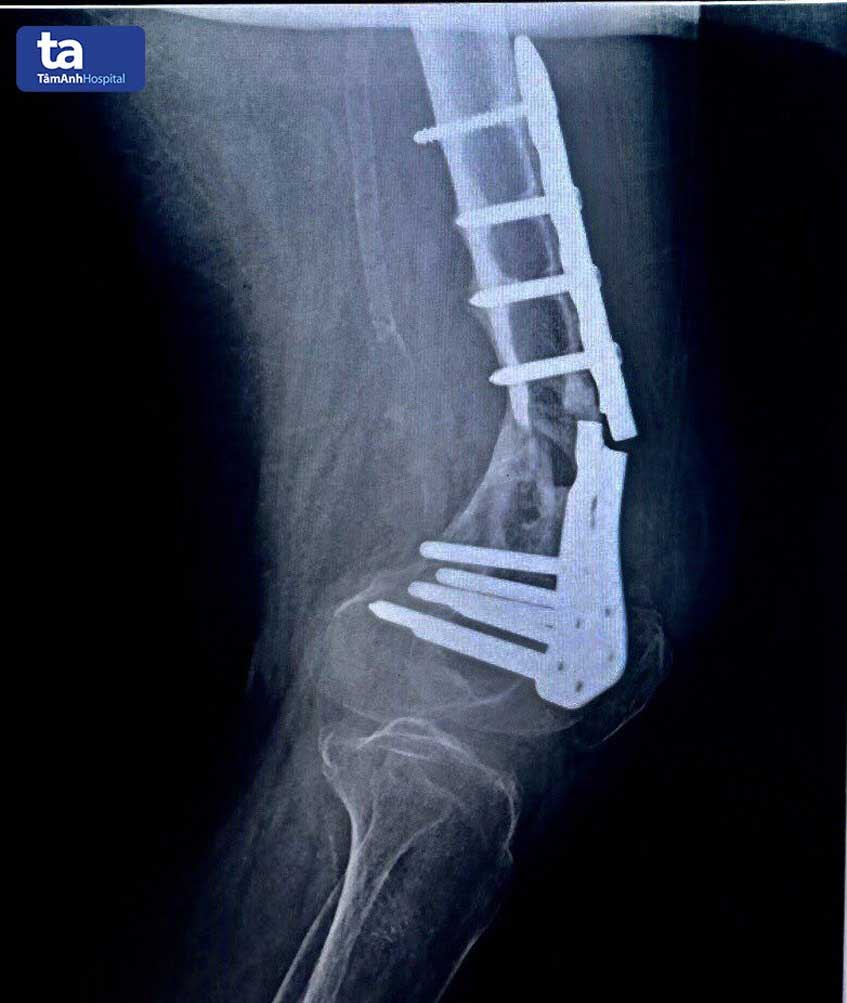

Vừa qua, Bệnh viện Đa khoa Tâm Anh TP HCM tiếp nhận một nữ bệnh nhân gần 70 tuổi bị gãy nẹp vít xương đùi/suy thận giai đoạn cuối, suy tim nặng (EF 44%), tiểu đường type II, tăng huyết áp, nhồi máu cơ tim cũ, tràn dịch màng tim lượng ít, xẹp L1 cần phẫu thuật thay nẹp xương đùi.

Bệnh nhân này đã cao tuổi, lại mắc các bệnh nội khoa kèm theo như bệnh tiểu đường, cao huyết áp, suy tim, suy thận nặng… Không may người bệnh gặp chấn thương do té ngã đã được phẫu thuật kết hợp xương bằng nẹp vít nhưng lại gãy nẹp phải phẫu thuật lại lần hai nhưng bị nhiều cơ sở y tế từ chối vì điều kiện sức khỏe không cho phép. Không từ bỏ hy vọng, người nhà bệnh nhân đã tìm đến Bệnh viện Đa khoa Tâm Anh để cầu cứu chuyên gia đầu ngành, với tâm nguyện có thể phẫu thuật an toàn, cho bệnh nhân cơ hội đi lại bình thường.

Cuối cùng, sau nhiều cuộc hội chuẩn, các bác sĩ Bệnh viện Đa khoa Tâm Anh quyết định dùng phương pháp gây tê thần kinh đùi cộng với thần kinh bì đùi ngoài để tiến hành phẫu thuật thay nẹp xương đùi.